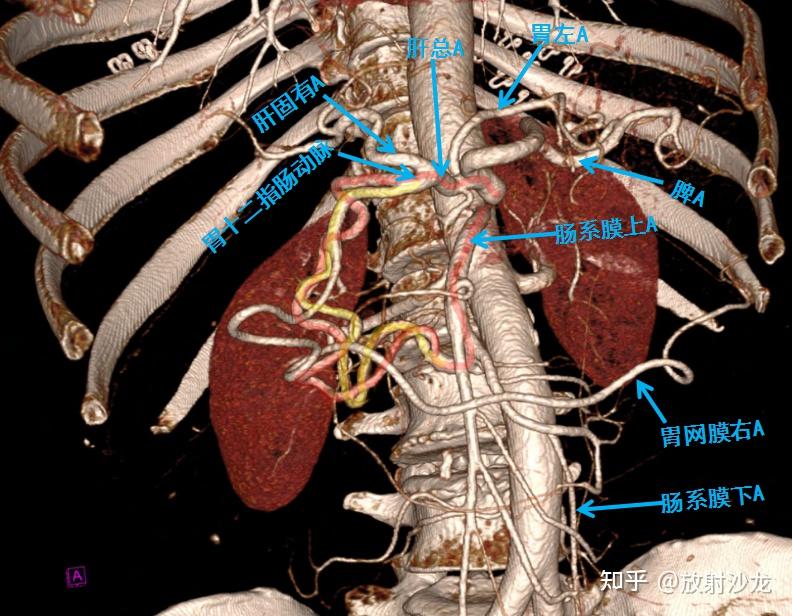

腹部血管cta解剖,腹腔干,肠系膜上动脉,肝总,固有,十二指肠-健康视频